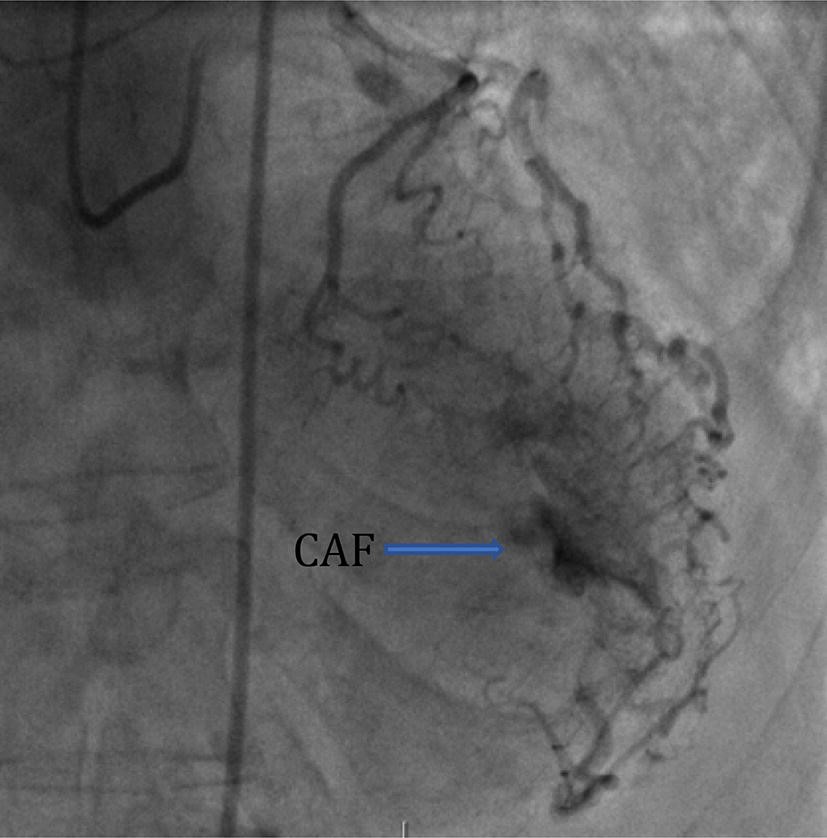

图1 回旋支-左心室caf